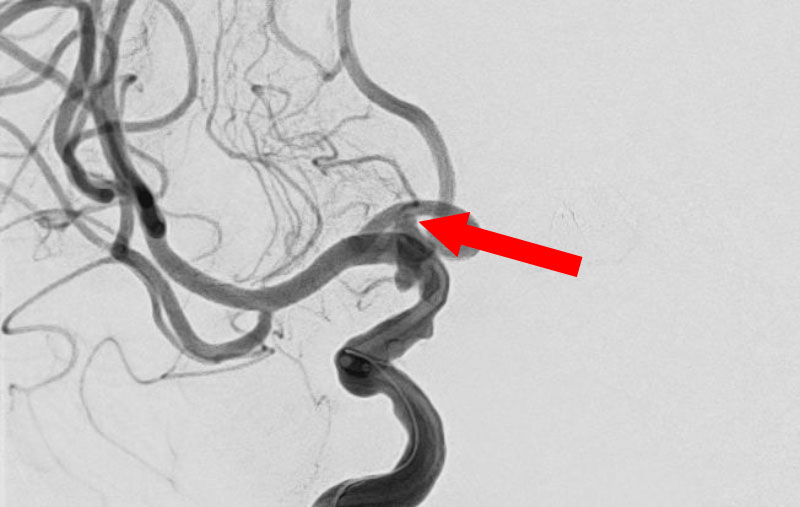

'25年11月

左内頚動脈脳動脈瘤

60代

大阪府の病院

No.1595 手術前

No.1595 手術中

No.1595 手術後